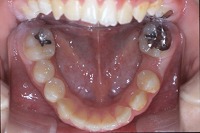

反対咬合と前歯が生えてこない事を主訴に来院された、10歳4か月の男の子です。診断「下顎骨の過成長による骨格性反対咬合で上顎正中の左方偏位と埋伏歯を伴う」1期治療で反対咬合の解消と埋まっていた前歯を牽引しました。